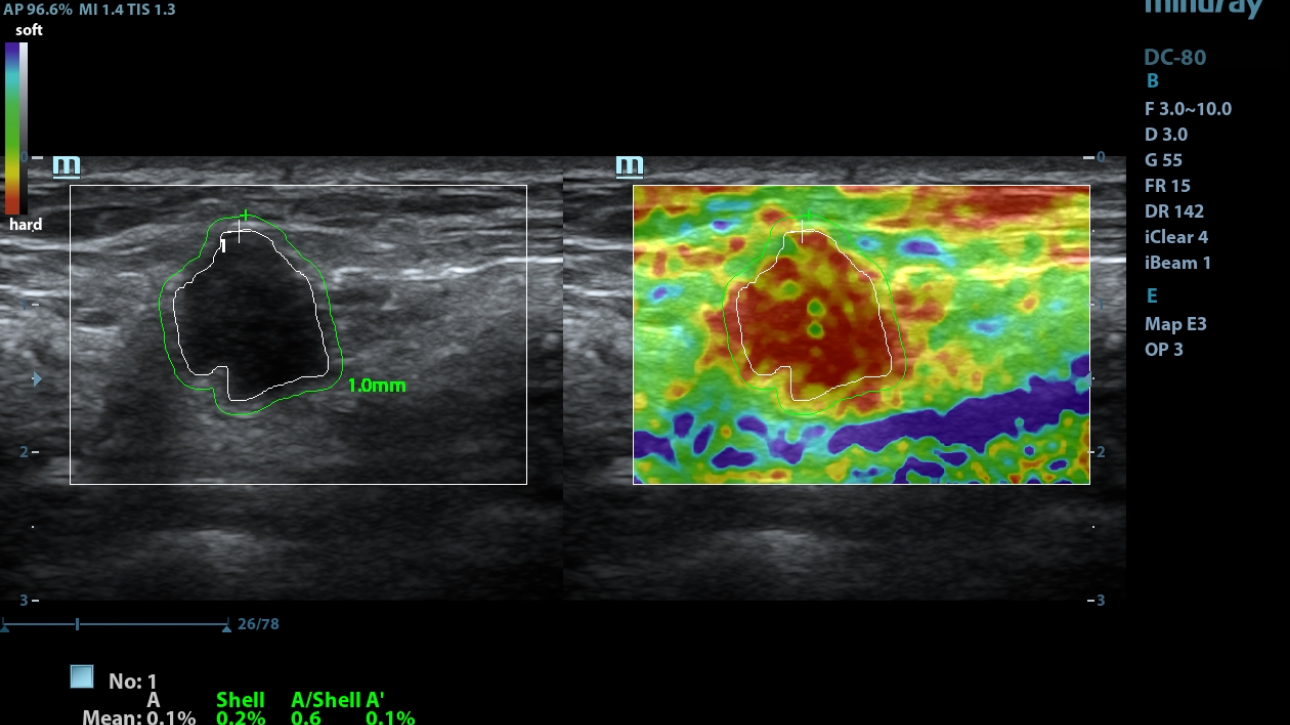

eXceptional Intelligence

Intelligence throughout entire workflow

Intelligence integrated in professional diagnostic tools for whole examination procedures,DC-80 with X-Insight provides exceptional intelligence integrated in professional diagnostic tools across wide applications and throughout whole examination procedures, from regular screening to further diagnosis and clinical follow up.